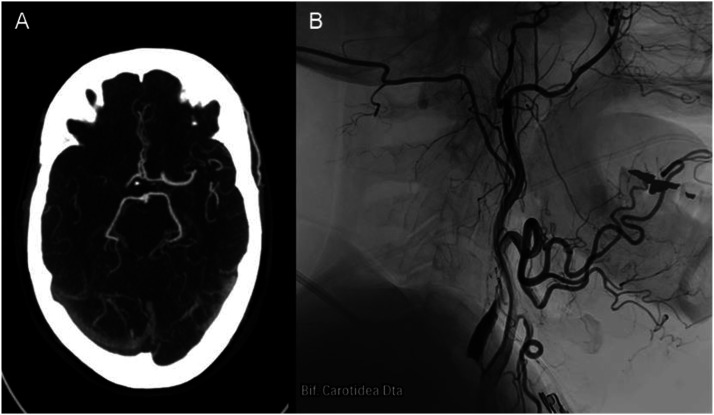

串联闭塞患者的血管内血栓切除术很少会导致颈内动脉破裂,从而引发蛛网膜下腔出血和死亡。然而,文献中很少报道和讨论这种并发症及其原因。我们描述了两例串联闭塞患者在血管内血栓切除术中发生颈内动脉破裂的病例。据推测,在再通之前,对远端病变的主要方法会造成盲区,在人工注射造影剂时会面临管腔内压力升高,超过血管的阻力,导致动脉壁破裂。为了防止这种并发症,有人提出了先治疗近端闭塞、通过微导管注入造影剂或将血管内支持导管缩回到颈内动脉狭窄近端等方法,并对这些方法进行了讨论。

Endovascular thrombectomy in patients with tandem occlusions can rarely result in the rupture of the internal carotid artery, leading to subarachnoid haemorrhage and death. However, this complication and its causes are rarely reported and discussed in the literature. We describe two cases of internal carotid artery rupture during endovascular thrombectomy in patients with tandem occlusion. It is hypothesised that the primary approach to the distal lesion, before recanalization, creates a blind alley that faces an intraluminal pressure increase upon manual contrast injection, surpassing the vessel's resistance and resulting in arterial wall rupture. To prevent this complication, approaches such as treating the proximal occlusion first, injecting the contrast through a microcatheter or retracting the endovascular support catheter proximally to the stenosis of the cervical internal carotid artery have been suggested and are discussed.